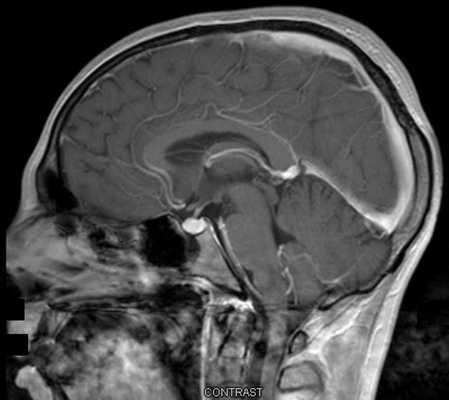

При подозрении на деформацию гипофиза необходимо провести специальное динамическое исследование с контрастным усилением для того, чтобы не пропустить даже самые мелкие образования в гипофизе. Контраст при проведении процедуры МРТ гипофиза вводится в определённые минуты и секунды сканирования. Проведение МРТ-диагностики гипофиза без применения контраста является малоинформативным.

Можно значительно повысить качество получаемых изображений гипофиза при проведении МРТ, если выполнить контрастирование, то есть ввести в кровеносное русло специальное контрастное вещество. При этом информативность проводимой томографии возрастает, позволяя уточнить локализацию, размер образования, его связь с окружающими структурами и интенсивность кровообращения. МРТ гипофиза с контрастированием практически всегда выполняют перед оперативным вмешательством по удалению аденомы или другой опухоли данной области мозга.

МРТ гипофиза с контрастом и без: А- гипофиз нормальных размеров (обведено кругом), В - симметричные кальцификации (стрелки)

Вопрос что лучше сделать: “МРТ гипофиза с контрастом или без?” - должен решить врач. Последний порекомендует приемлемые для получения качественных изображений характеристики аппарата: сканы, сделанные с помощью низкопольных аппаратах с открытым контуром малоинформативны. Оптимально пройти обследование на томографе с мощностью от 1,5 Тесла.

Учитывая размер гипофиза (с горошину), МРТ преимущественно выполняют с введением контрастного вещества. В качестве красителя используют растворимые соли (хелаты) гадолиния, которые не представляют опасности для организма и при накоплении тканями обеспечивают лучшую визуализацию. Побочные эффекты встречаются менее, чем у 1% людей. Контрастирование ограничивают: